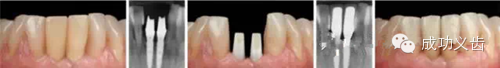

图5.Nobel Replace种植前。联合正畸治疗,以常用的Nobel Replace系统,来修复这个病例。

图6.Nobel Replace种植后。可见缺失的双侧切牙好像从牙龈里生长出来的一样。漂亮的外科、精心的软组织维护、极致的修复、和完善的口内摄影,成就了这个完美的病例。